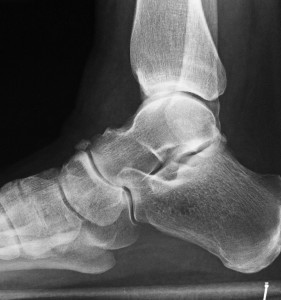

Many people with heel pain may have a bone spur present under the heel, but this is rarely the cause of the pain, or more likely to be a result of the condition.

The most common cause for heel pain is plantar fasciitis, an inflammation of a band of tissue (the plantar fascia) within the arch of the foot that inserts into the heel bone. This commonly causes pain when getting out of bed in the morning, and may recur through the day. Often patients described the feeling of a ‘stone bruise’ under the heel. The treatment of plantar fasciitis can involve the use of taping, stretching, anti-inflammatory medication, foot orthoses and ultrasound (shockwave) therapy.